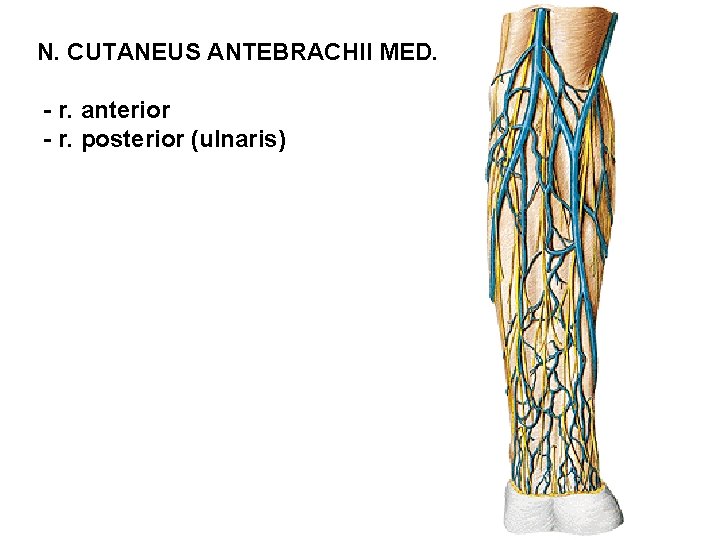

N. CUTANEUS ANTEBRACHII MED. - r. anterior - r. posterior (ulnaris)